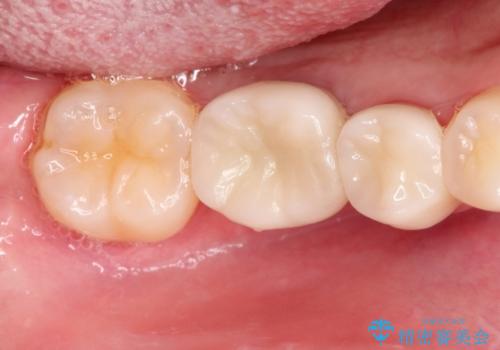

- 右下の奥歯の調子がよくないとのことで来院されました。

レントゲン・口腔内診査をお行い、保存が難しいことがわかりました。

抜歯後インプラントをする計画としました。

見た目では問題がなさそうでも、レントゲン撮影・診査を行うと状態が悪くなっていることがあります。